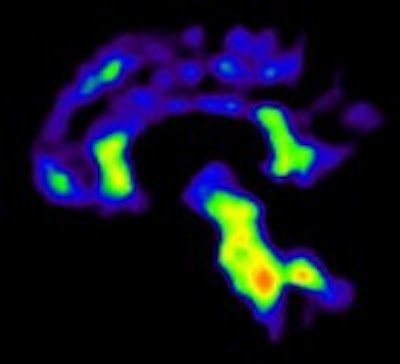

The image on the left shows PiB binding (red) in the cortical regions of the brain to indicate the presence of amyloid plaque, while the image on the right shows PiB binding to white matter (red), which signifies a negative result. All images courtesy of Dr. Rik Ossenkoppele.PiB-PET scans were positive in 40 (61%) of 66 patients with clinical Alzheimer's and in five (28%) of 18 patients with clinical frontotemporal dementia. FDG SUV patterns matched the clinical diagnosis in 58% of patients with Alzheimer's and 33% of patients with clinical frontotemporal dementia, the authors noted.